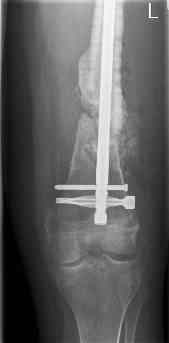

feb 07: retrograde nail + bone graft + BMP

may 07: dynamisation nail

sept 07: locking screw removal (max. dynamisation reached)

nov 07: persistant non-union distal femur; other fractures healed uneventfully.